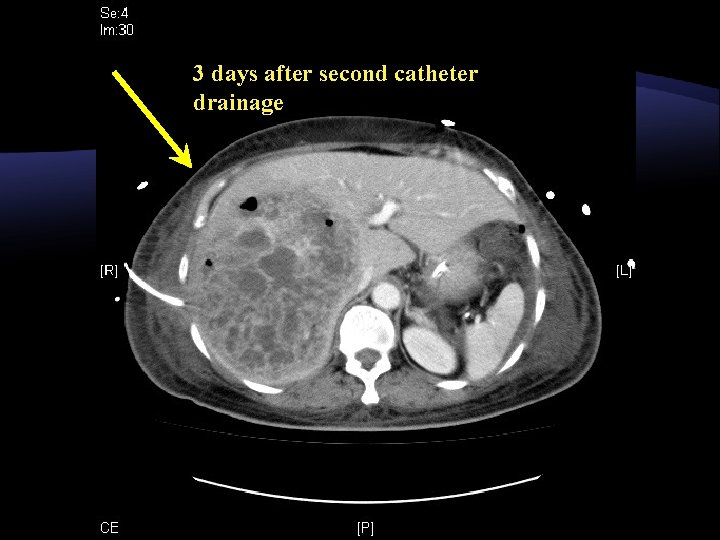

CT on D 7 after drainage Right lobe liver abscess remained static in size

3 days after second catheter drainage